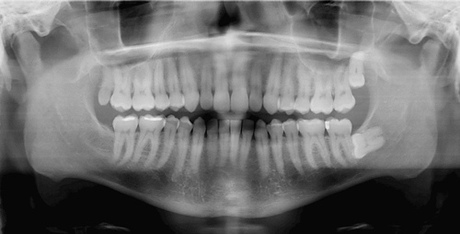

Also, people who reported getting a yearly panorex exam -- in which an X-ray is taken outside the mouth and shows all the teeth on one film -- were 2.7 to three times more likely to develop cancer, said the study.